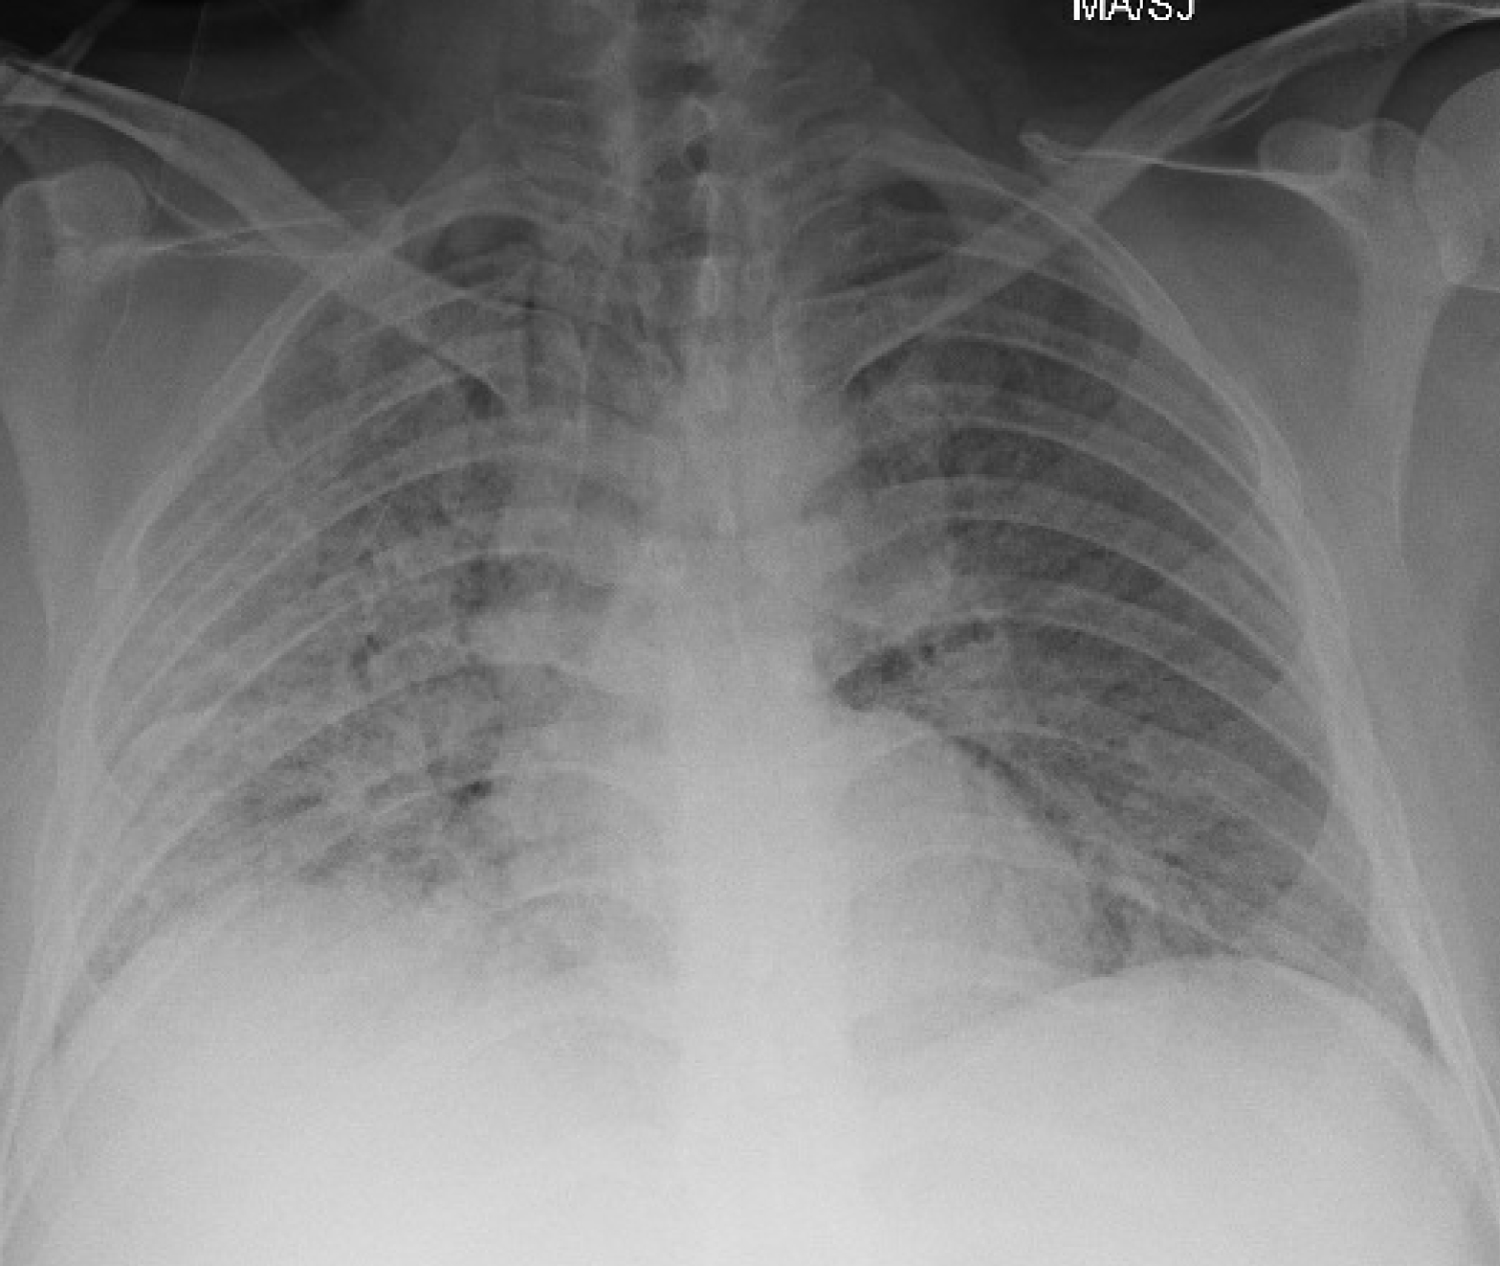

A 37-year-old obese, Hispanic male, never smoker with no significant medical history was admitted with five days of cough, fever, and dyspnea. On admission, he was afebrile, tachycardic with a heart rate of 108 beats per minute, tachypneic with a respiratory rate of 31 breaths per minute and oxygen saturation was 92% on 100% NRB. He was found to have severe Acute Respiratory Distress Syndrome secondary to SARS-CoV-2 viral pneumonia, with a PaO2:FiO2 ratio of 80. Admission labs revealed normal WBC count, acute kidney injury with creatinine 1.7 mg/dL. CRP elevated at 5.5 mg/dL, LDH elevated at 738 U/L, D-dimer elevated at 1.29 ug/mL and ferritin elevated at 489 ng/mL. His chest X-ray showed bilateral diffuse infiltrates. He was treated with a course of hydroxychloroquine, azithromycin, and methylprednisolone. He received tocilizumab and convalescent plasma. He continued to require 100% NRB mask to maintain his oxygenation. On day 14 of his hospitalization, he had persistent hypoxemia requiring 100% NRB and 6 liters per minute nasal cannula used in tandem. Chest X-ray showed pneumomediastinum (Figure 2). He had CT thorax done which showed complete ground glass opacification of bilateral lungs, diffuse pneumomediastinum, and small amount of pneumopericardium. No significant underlying bullous lung disease was noted. He was managed conservatively, and was noted to have slowly decreasing oxygen requirements. He was discharged home after a 27-day hospitalization on 2 liters per minute nasal cannula oxygen. He was followed up in pulmonary clinic with continued improvement in his symptoms. A repeat chest X-ray done three weeks after discharge showed improved pneumomediastinum and significant improvement in bilateral consolidations.

Figure 2: Pneumomediastinum. View Figure 2